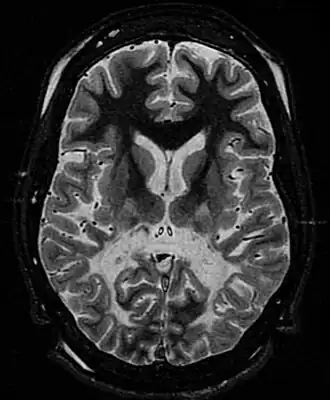

![]() Sustancia blanca, con volumen reducido y aumento de la intensidad de la señal. La sustancia blanca anterior está respetada. Las características son compatibles con la adrenoleucodistrofia ligada al cromosoma X. | ||